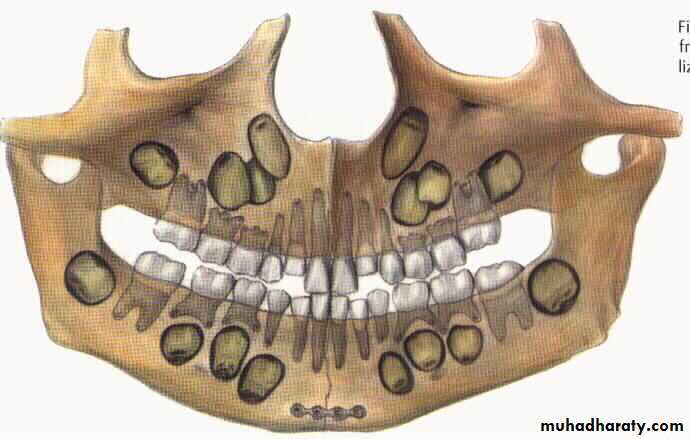

It is indicated in the young children and for edentulous patient.In children below 12 years age cap splints are made and circumferential wiring done so that injury to the tooth buds can be avoided.

Similarly in edentulous patient , who also have a compromised blood supply, and no teeth to give inter maxillary fixation, this technique is very helpful.

Fracture mandible in children

Close reductionOpen reduction and fixation

Plating at the inferior border

Resorbable plates